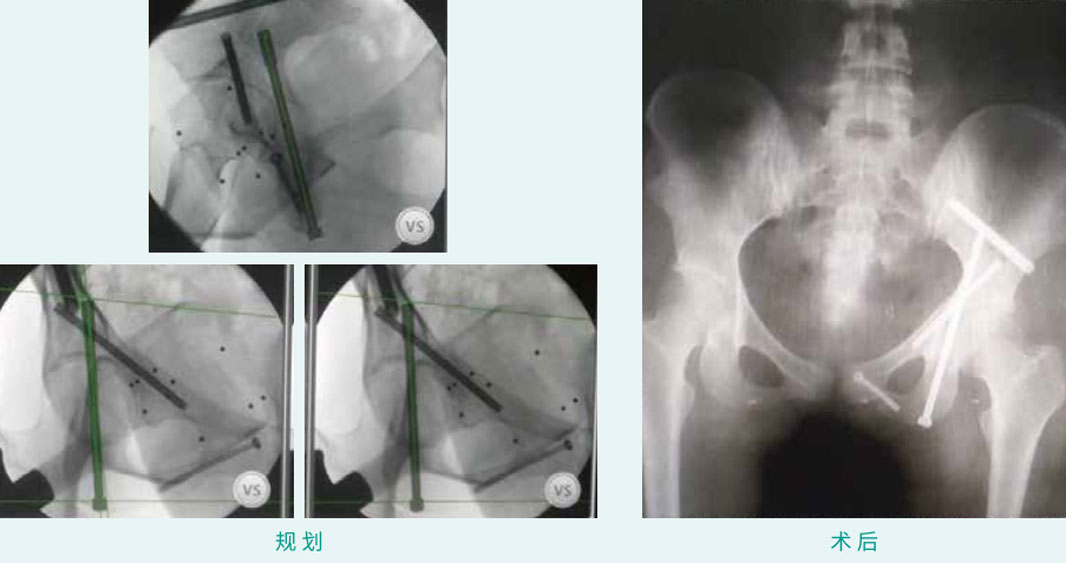

天玑? 辅助骨盆通道螺钉(前柱、后柱、耻骨下,,,,,,,,LC-2型)经皮空心螺钉内牢靠术

基本情形:患者女,,,,,,,,20岁,,,,,,,,骨盆髋臼骨折

机械人累积用时:45分钟

植入物:4枚空心螺钉

病例泉源:天津医院 贾健 田维